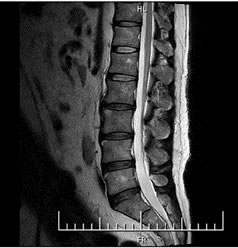

検査画像

MRI(Magnetic Resonance Imaging:磁気共鳴画像)とは、磁力と電波の力によって、人体のあらゆる部分の断面像を撮ることができる画像診断装置です。頭から足先まで全身の検査ができ、非常に精度の高い検査を行うことが可能です。